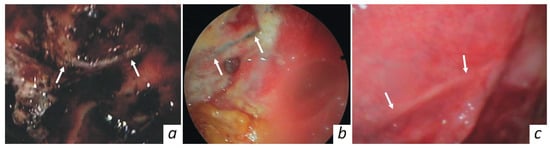

In the follow-up period, the reparative process in the treated orbital area was endoscopically monitored, as shown in Figure 4. On the fifth day the implantation zone was covered with fibrin. The implant site is seen to be not covered with tissues of the recipient area, whereas clots and granulation tissue are pointed out. On the twenty-first day, the wound surface seems to be completely cleared of necrotic masses and fibrin. Granulation tissue formation continued, and epithelialisation at the wound margin was noted. The KTNM was completely epithelialized within one month after surgery. No inflammatory changes were observed in the recipient zone.

Figure 4. Endoscopic view of the repaired orbital area, taken at (a) 5, (b) 21, and (c) 35 days after surgery.